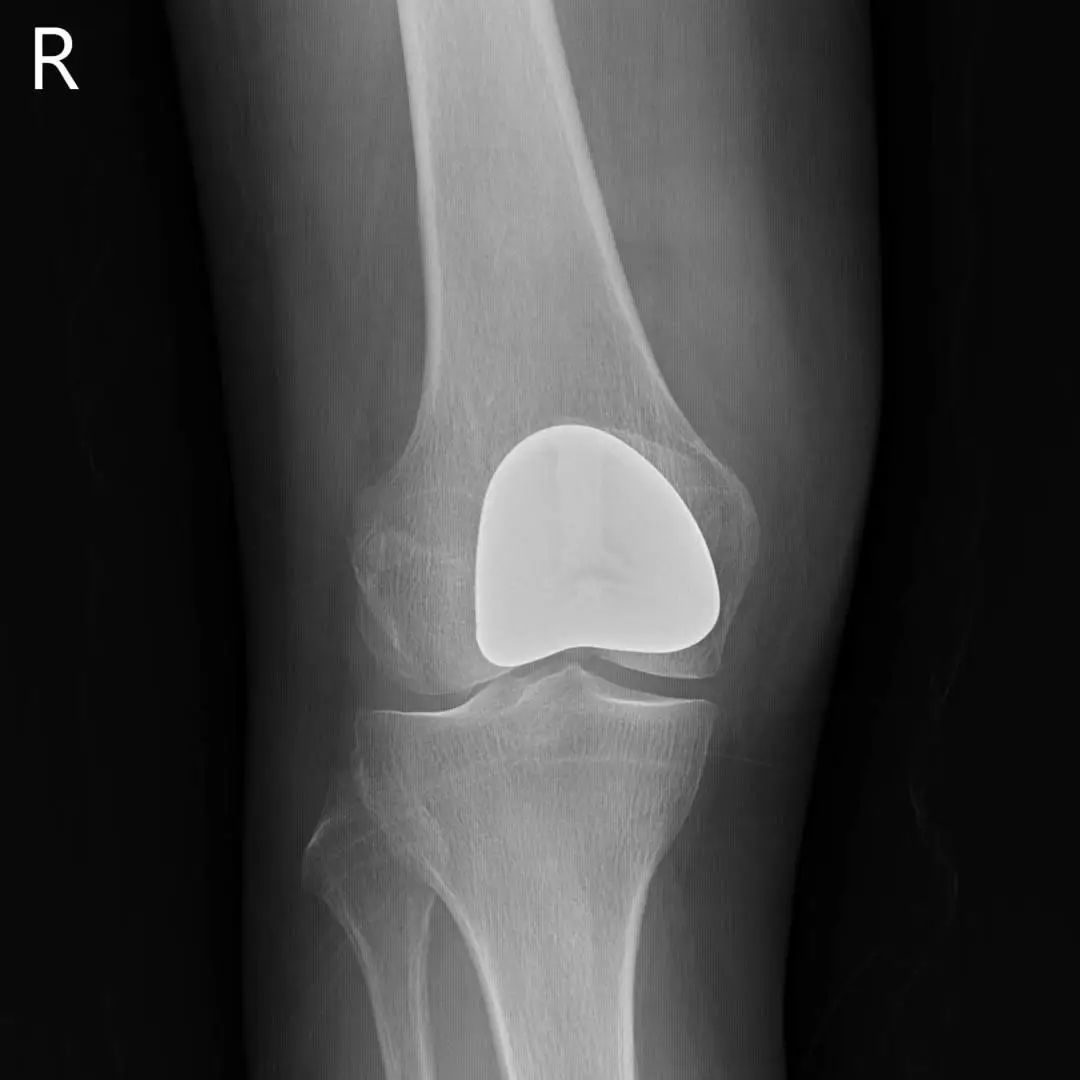

67岁的邵阿姨,双膝关节疼痛10余年,疼痛主要集中在屈伸膝关节时髌骨下。长期口服及外用药物治疗效果欠佳,反复加重,双膝的x线检查提示主要为髌股关节的退行性骨关节炎。程飚主任结合患者症状,影像学结果,体格检查,发现邵阿姨主要问题集中在髌股关节,膝关节间隙,内外侧髁,胫骨平台均可,为解决邵阿姨痛苦,尽可能保留关节,程飚主任决定对邵阿姨进行双侧膝关节的髌股关节表面置换,截骨量较少,邵阿姨第二天就能下地活动了,屈伸关节也不痛了,对手术疗效表示非常的满意。

部分膝关节置换手术目前已是非常成熟的治疗方法,亦属于保膝治疗的一种。主要包括单髁置换,髌股关节置换。单髁置换主要把膝关节内侧髁或者外侧髁表面已经磨损的部分替换成金属的假体和高分子聚乙烯耐磨垫片。髌股关节置换主要把髌股关节表面已经磨损的部分替换成金属的假体。

病变局限于髌股关节的患者,可行髌股关节表面置换;

同时有髌股关节及单侧髁的病变,可行单髁+髌股关节表面置换。